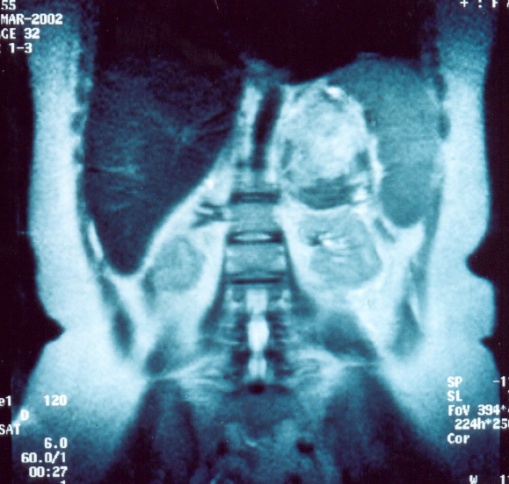

Αριστερό περινεφρικό αιμάτωμα και δεξιό αιμάτωμα λαγονοψοΐτη — αντιπηκτική αγωγή (Ευγενική παραχώρηση Dr. V. Penopoulos)